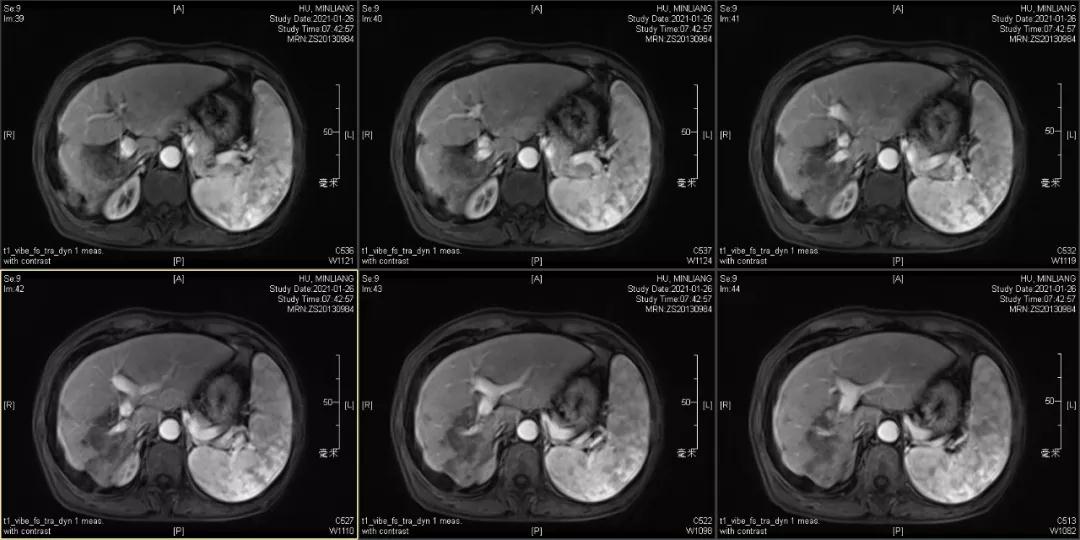

Δ肝脏MRI,最大肿瘤18.4cm

肿瘤学评估(用药后2个月对比6个月):肝内主瘤明显缩小,动脉期强化降低;子灶消失;门脉右支癌栓明显缩小坏死;肺转移灶缩小,大部分消失。

2021-01-25

Δ治疗过程中病灶影像学变化